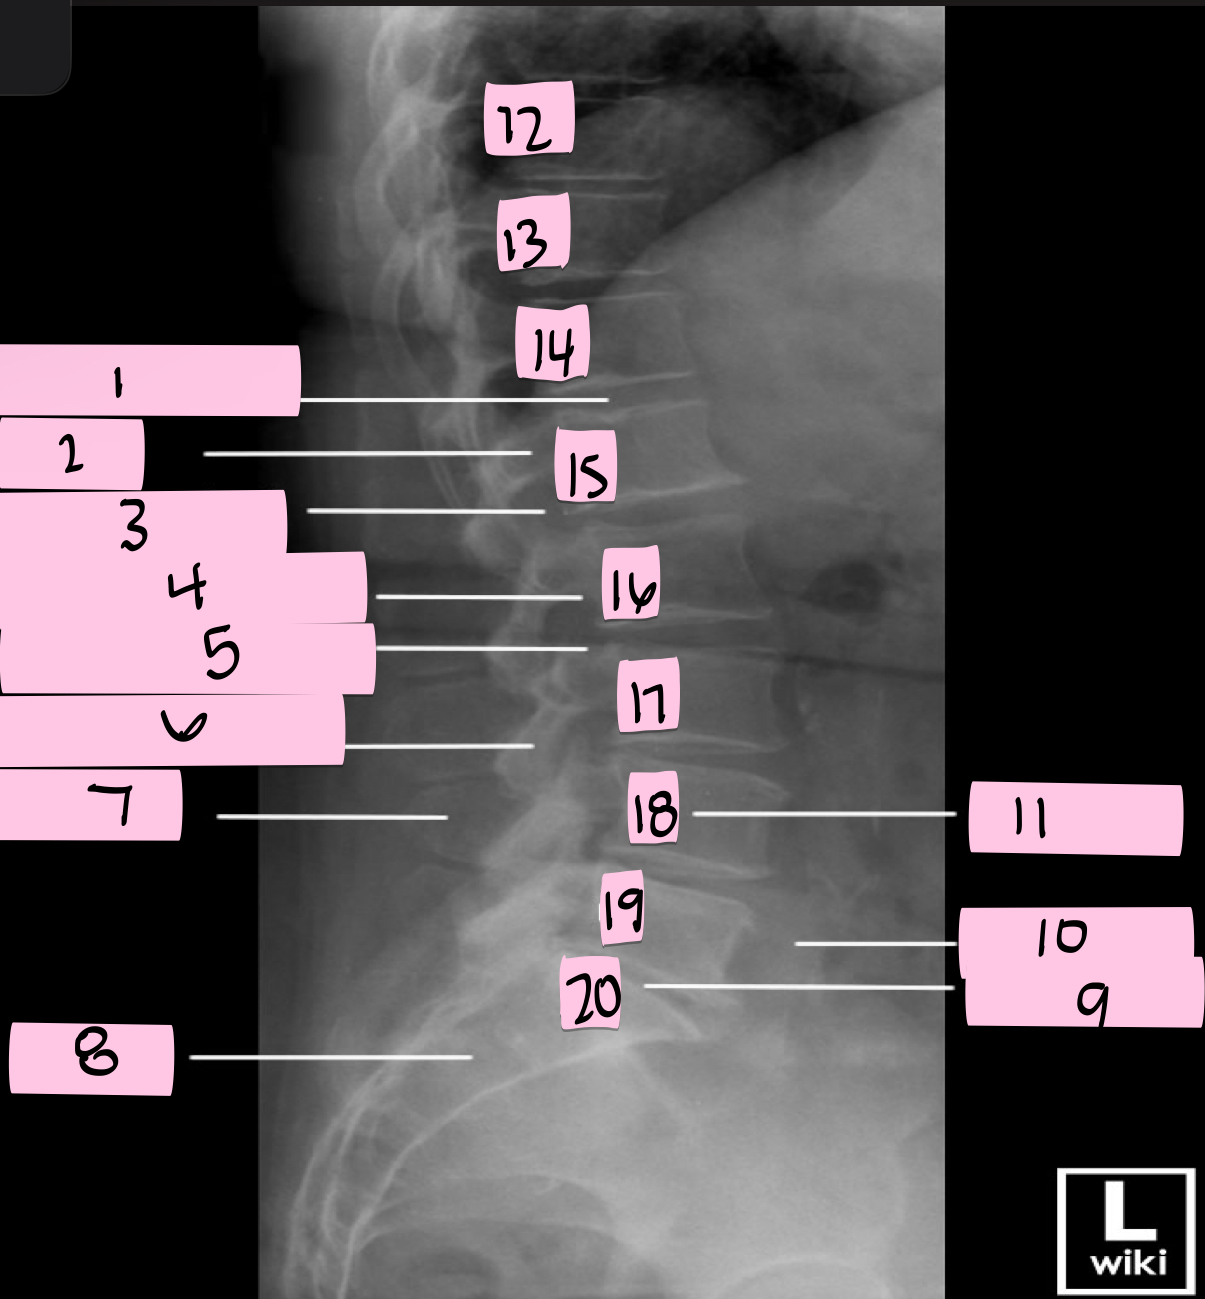

What is 1 pointing to?

Intervertebral disk

What is 2 pointing to?

Pedicle

What is 3 pointing to?

Intervertebral foramen

What is 4 pointing to?

Inferior vertebral notch

What is 5 pointing to?

Superior vertebral notch

What is 6 pointing to?

Inferior articular process

What is 7 pointing to?

Spinous process

What is 8 pointing to?

Sacrum

What is 9 pointing to?

L5 S1 joint

What is 10 pointing to?

Iliac crest

What is 11 pointing to?

Vertebral body (L4)

What is 12 pointing to?

T10

What is 13 pointing to?

T11

What is 14 pointing to?

T12

What is 15 pointing to?

L1

What is 16 pointing to?

L2

What is 17 pointing to?

L3

What is 18 pointing to?

L4

What is 19 pointing to?

L5

What is 20 pointing to?

S1